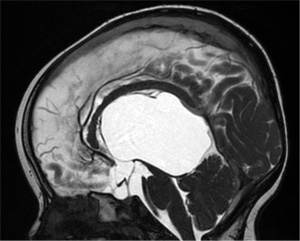

小児神経外科は、赤ちゃん(場合によってはお母さんのお腹にいる赤ちゃんも含めて)から思春期までの、成長過程にあるこどもの脳と脊髄疾患の外科治療を受け持ちます。脳神経外科の一専門領域ですが、新生児からいわゆるAYA世代までの、全ての疾患領域をカバーしないといけないという奥行きがあります。小児で、成人と異なる一番の特徴は“成長”の要素があることです。外科治療を行うことで、未熟な脳や脊髄の成長・発展を促すと同時に、成長に伴い追加手術が必要になることも織り込んで長期的な治療計画・手術方法の選択を考える必要があります。

小児神経外科で治療する疾患は、大きく分けて水頭症や二分脊椎のように先天異常を背景に持つ病気、脳腫瘍などの腫瘍性病変、大人ほど多くはありませんがモヤモヤ病や脳動静脈奇形などの脳血管障害、頭部外傷、その他の疾患となります。それぞれ、基本的な手術から複雑な手術までありますが、手術の役割は状況によって一つ一つ異なってきます。先天異常による病気では、先天異常そのものを治すことはできなくとも二次的に派生する病態・症状の出現を予防あるいは治療することが目的になります。また、異常をきたした神経組織を可能な限り形態的に修復して神経機能の改善を目指すこともあります。腫瘍の手術でも、可能な限り一回の手術で摘出することを目指しますが、腫瘍の性状・部位によっては計画的・段階的に手術を進めていく必要が生じることもあります。他の治療法との組み合わせも大切になります。さらに、一部には年齢依存性に増大する腫瘍もあり、腫瘍との共存を図るという発想が必要になることもあります。治療は必ずしも一筋縄で論じることができないのです。

1. 水頭症

基本はVPシャント(脳室腹腔短絡)術で治療しますが、できるだけ神経内視鏡による治療(第3脳室開窓術、脈絡叢焼灼術など)を目指しています。嚢胞性疾患を伴う場合は、神経内視鏡による開窓術が第一選択になります。水頭症は小児神経外科の基本的手技です。基本的手術だからこそ、合併症のない確実な手術を行います。水頭症治療の術式選択にあたっては、ご両親の希望にも配慮して治療法を決定するようにしています。